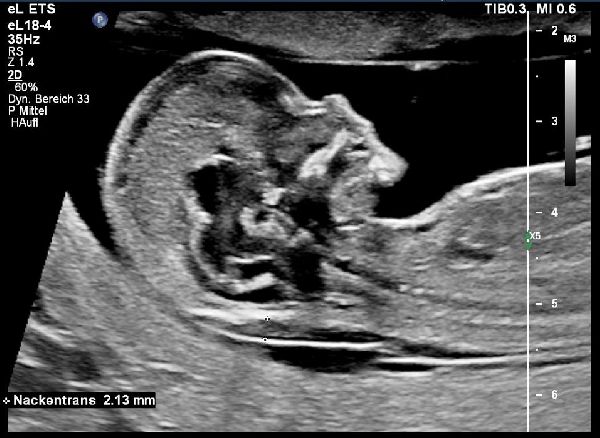

In der Pränatalen Diagnostik bieten wir alle Verfahren mit High-End-Geräten der neuesten Generation an: Ersttrimesterschall, Fehlbildungsschall, fetale Echokardiographie, Dopplersonographie, 3D/4D-Ultraschall sowie Punktionen der Fruchthöhle (z.B. Amniozentese, Chorionzottenbiopsie). Auch die cffDNA-Tests sind bei uns bereits fest etabliert.

Die passende Begleitung

Innerhalb der Pränatalmedizin haben wir uns, neben gängigen 3D-Ultraschall- und Doppler-Ultraschalluntersuchungen, auf die Früherkennung von Fehlbildungen und die Betreuung bei Risikoschwangerschaften spezialisiert. Dazu haben wir uns zum einen auf das erweiterte Ersttrimesterdiagnostik (u.a. mit Nackentranzparenzmessung) spezialisiert sowie gegebenenfalls die weitere Abklärung des Kindes mittels cffDNA-Test, Amniozentese oder Chorionzottenbiopsie. Zum anderen bietet unsere Praxis interdisziplinäre Begleitung bei Zwillings- oder Drillingsgeburten, Fehlbildungen oder Wachstumsverzögerung des Kindes. Unser Praxisteam, die Ärzte für Frauenheilkunde und Geburtshilfe und die Ärzte für Humangenetik, freuen uns auf Sie, Ihr Kleines und Ihre Fragen.